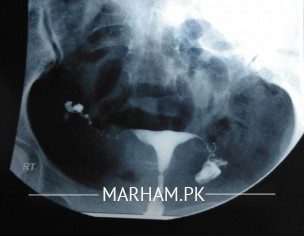

Hi, I got my HSG done last year. The report says that both the fallopian tubes are patent. I visited many doctors since then and all considered the report valid (none checked the film). However, on the basis of the report, my doctor has scheduled an IUI round this month. Recently, I met a doctor who checked the film and said that it seems that the tubes are not patent and laparoscopy should be done to check for it. Now the problem is if the tubes are not patent, there is no point of even getting an IUI. I am attaching the report as well as the films. Want an opinion on either I should start taking my ovulation induction pills and continue with the IUI procedure or not take my ovulation induction medicines and wait to see my doctor (the appointment is scheduled next week).

on both side spilled dye can b seen... its normal hsg. still if you want to take second opinion then report can be checked by sime radiologist... yahan tak bat laparoscopy ki hai it us best to diagnose so many problems responsible for not conceived till now.. including tubal patency

spill is seen on both sides.

U tubes r patent.

Eens to have some old infection causing ur tubes beaded in appearance

IUI will fail

Please take opinion from expert radiologist. At least one tube is patent.